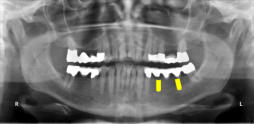

Beispiele für komplexe implantologische Versorgungen aus unserer Gemeinschaftspraxis

(Planung / Endversorgung -- als Röntgenaufnahmen)